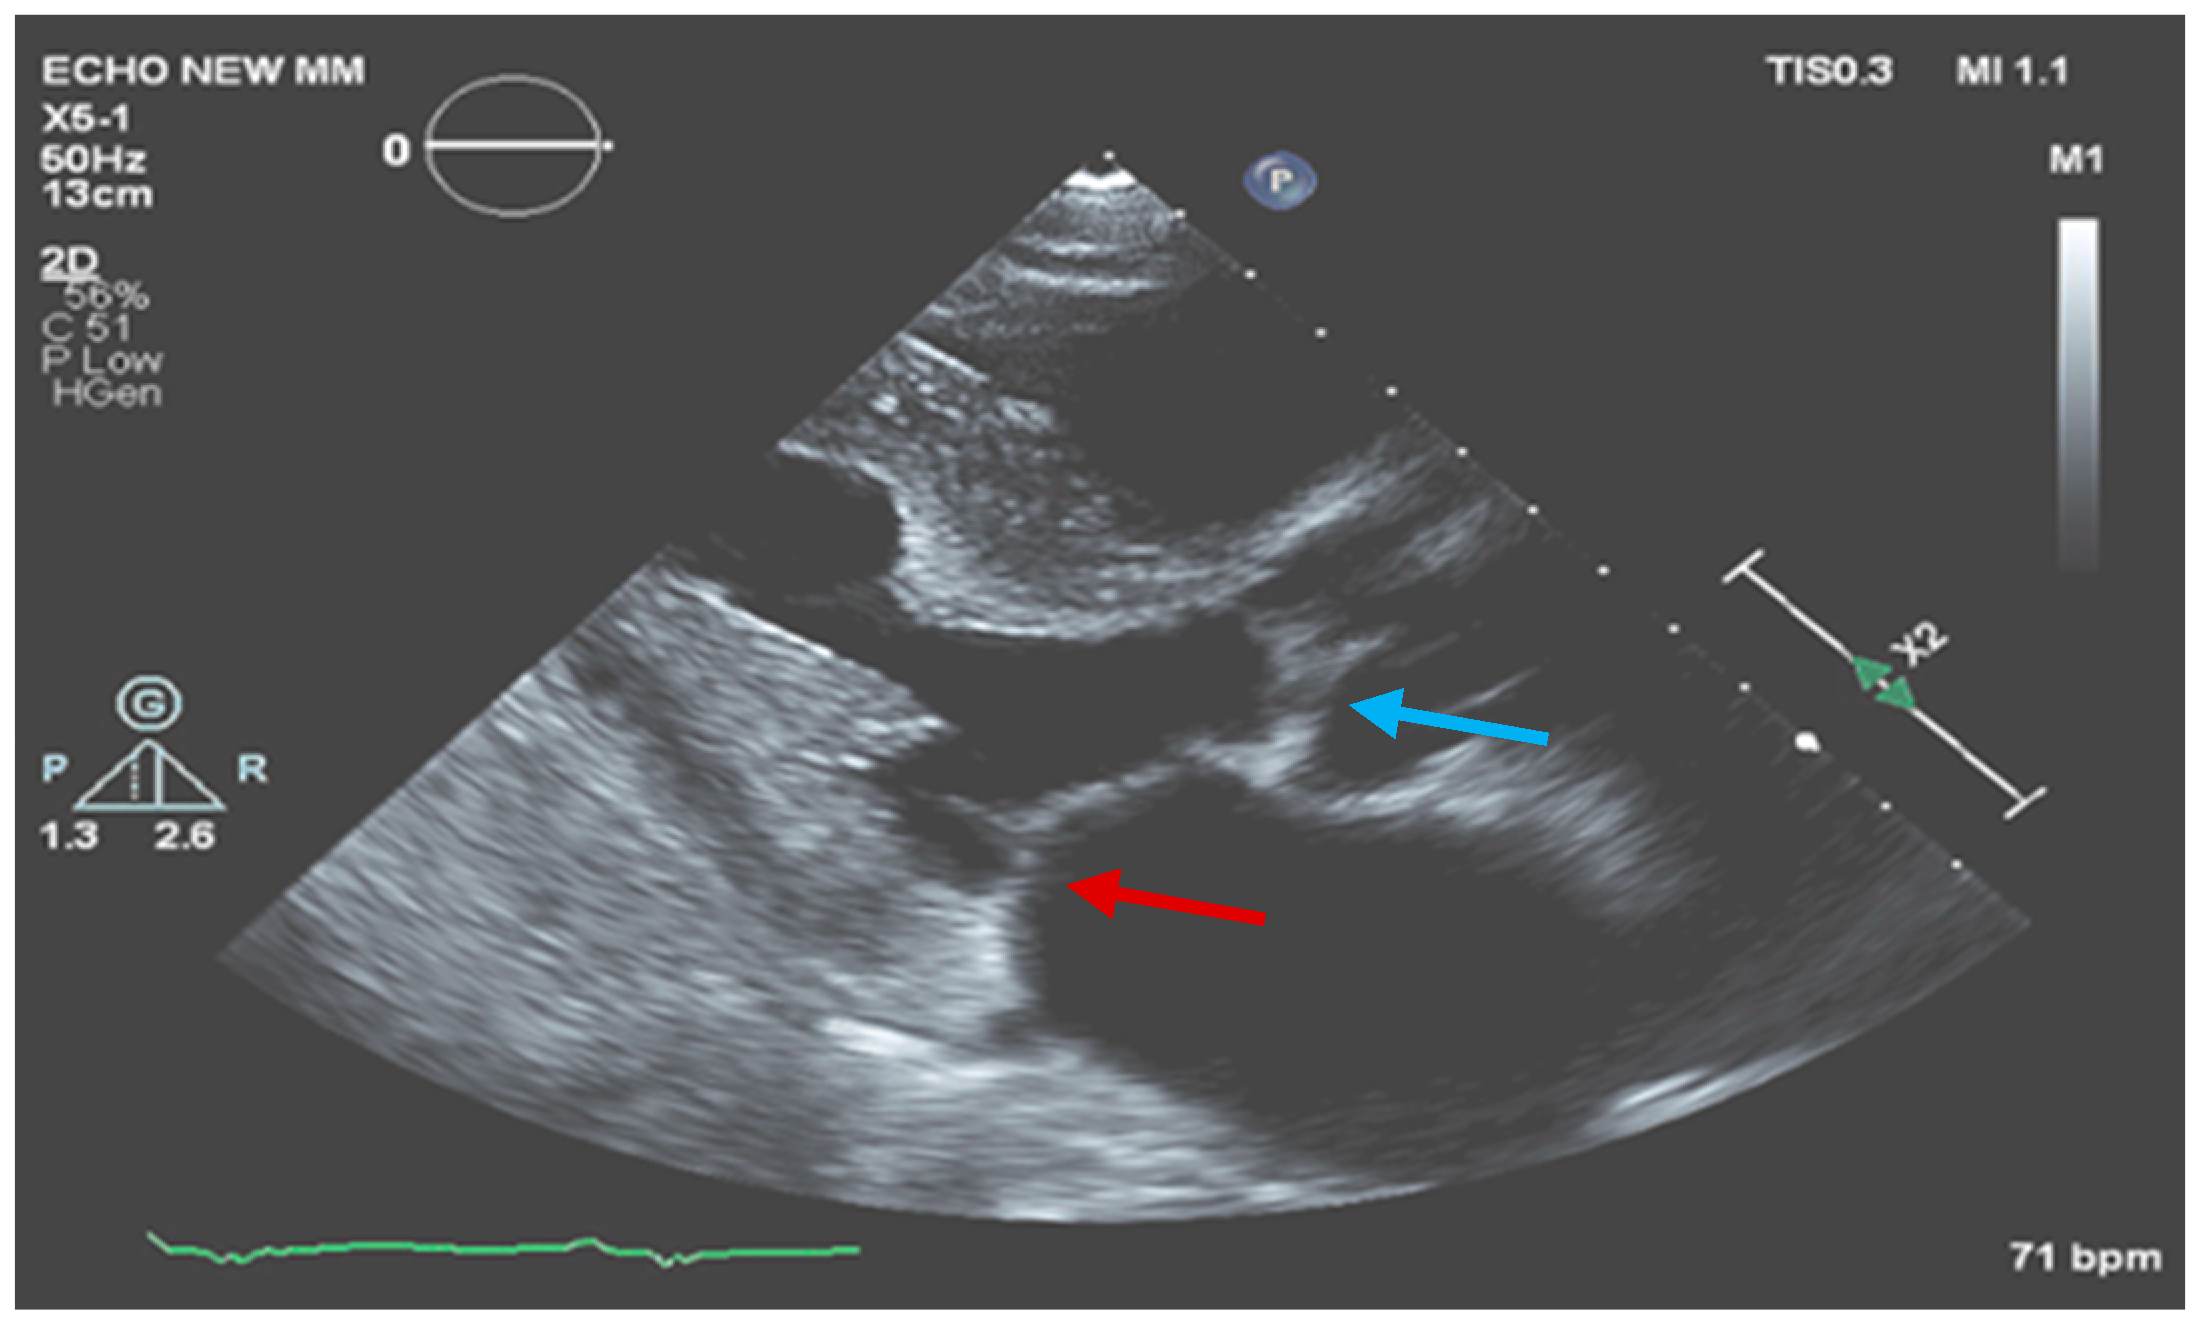

One month later, the patient was examined in our outpatient infectious diseases clinic. He was in a good clinical condition without fever, chills, weight loss, effort dyspnea, or signs of heart failure. He completed six weeks of the antibiotic regimen for enterococcal endocarditis and is currently continuing doxycycline and hydroxychloroquine with good adherence and tolerance. Repeated TEE showed normal LV and RV function, moderate mitral regurgitation, small soft mass (0.5 × 0.5 cm) on the atrial aspect of the posterolateral leaflet of the mitral valve, and normal aortic valve with no vegetation (Figure 3).

Figure 3.

Mitral valve (red arrow) and aortic valve (blue arrow) with significant improvement in the size of the vegetations.